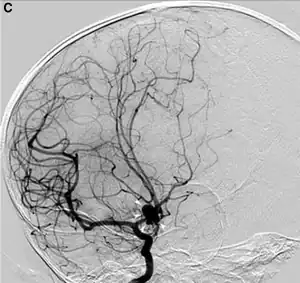

O exame padrão ouro para detecção de aneurisma cerebral não é a tomografia ou a ressonância magnética, e sim o cateterismo cerebral de 4 vasos (angiografia digital).

O diagnóstico, de acordo com a localização da artéria, pode ser feito por exame físico no consultório. Pela apalpação da artéria (quando isso for possível) o médico pode avaliar se há dilatação que mereça investigação maior, realizada por meio de exames como ultrassonografia, tomografia computadorizada, ressonância magnética ou arteriografia.